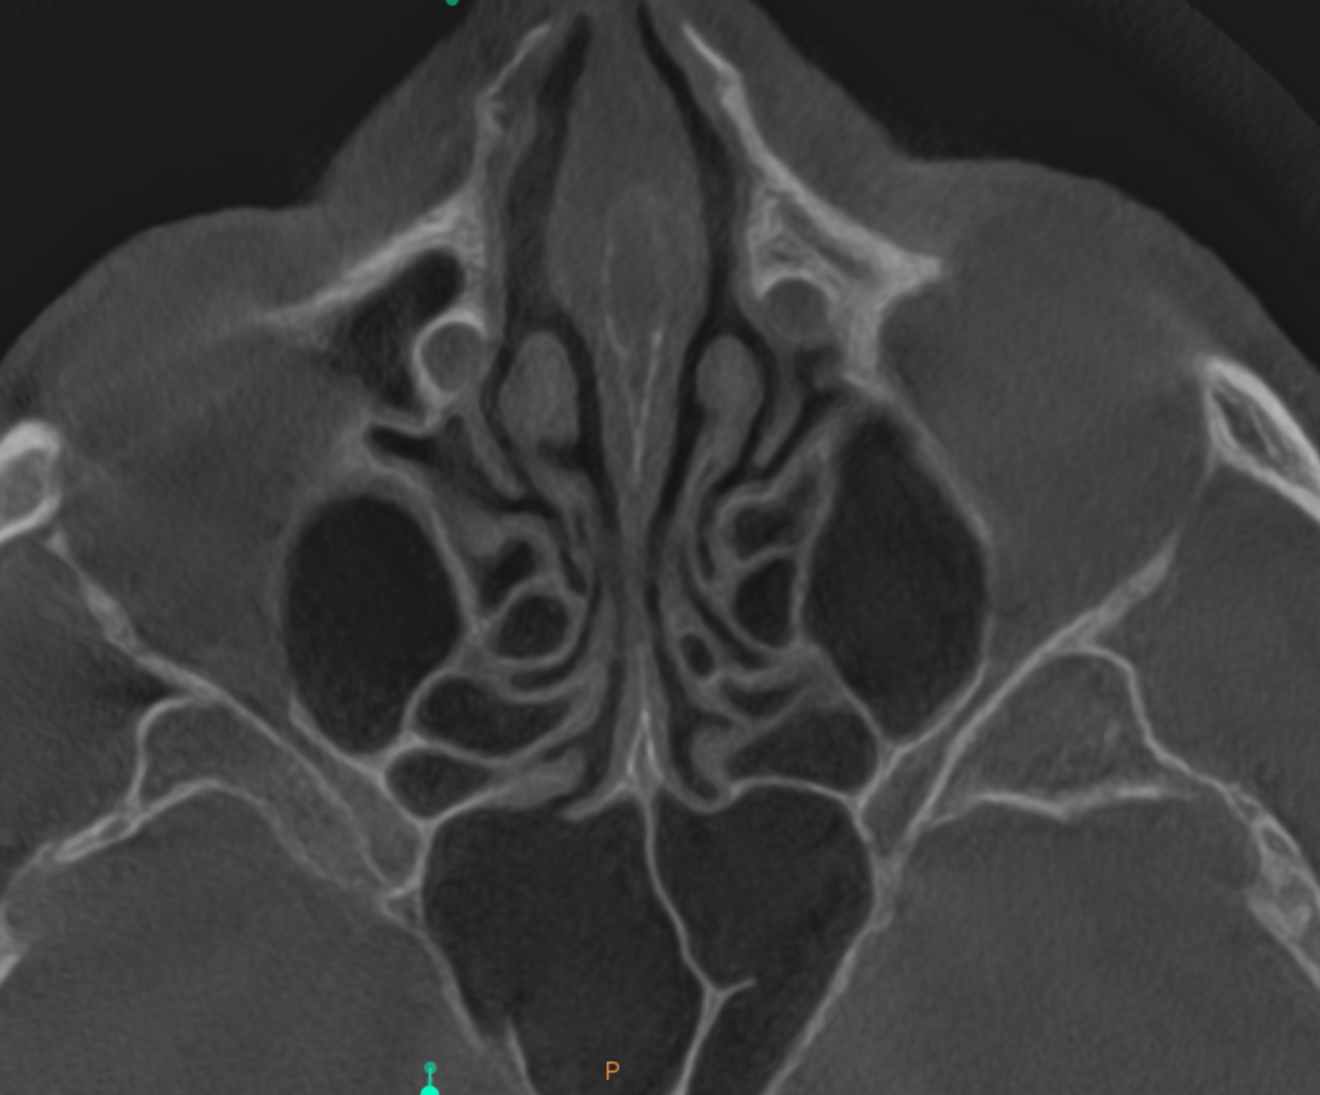

Fig. 3: Large-volume CBCT scan, frontal cross-section showing increased radiopacity in the paranasal sinus area.

The extent of the inflammation was shocking (Figs. 2a & b). Not only the maxillary sinus (Fig. 3) but the ethmoid and sphenoid sinuses too were involved, and the inflammation had spread towards the right cavernous sinus as well (Fig. 4). At this point, extraction may have been the first choice for most dental clinicians, but we had to keep in mind that invasive treatment may have increased the risk of cavernous sinus thrombosis, a potentially avoidable possibility. There are very few circumstances under which a dental procedure can cause very severe or even lethal consequences, but this case approached such a situation.